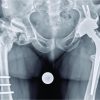

The control X-ray (Fig. 2) revealed acceptable reduction, and the patient was referred to follow-up at the outpatient consultation. The conservative treatment was kept for 25 days, with apparent fracture healing on the X-ray (Fig. 3), but the patient presented limitation on active flexion of the finger which was interpreted as a sequel of the immobilization. Thus, he was referred for physical therapy rehabilitation. Six weeks after the initial trauma, the patient was observed at the emergency department for new right-hand trauma. On examination, no active flexion of the third phalanx of the second finger of the right hand was noticed. The X-ray didnot show any new fracture (Fig. 4).